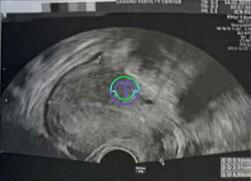

开始治疗前的基础超声波与激素检查结果

初始卵子数量:17 个

右侧卵巢:7 个

左侧卵巢:10 个

激素结果

LH = 15.80 mIU/mL → 偏高,存在卵泡过早排卵的风险

E2 = 47.60 pg/mL → 表明卵巢储备功能仍在可接受范围内